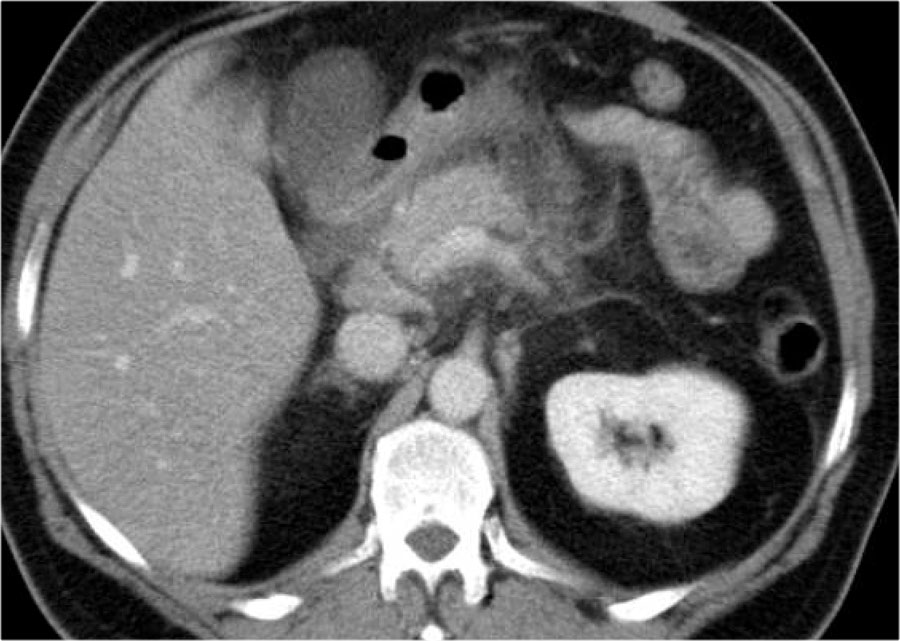

Hoại tử nhiễm trùng (2)

Ở bệnh nhân này, tụy ngấm thuốc bình thường với các ổ hoại tử cấp tính không đồng nhất có vách ngăn xung quanh, có tỷ trọng dịch và mỡ.

Đây có thể là hoại tử mô quanh tụy.

Hai tuần sau, xuất hiện các bóng khí trong ổ dịch quanh tụy, phù hợp với ổ hoại tử cấp tính nhiễm trùng.

Bệnh nhân này được phẫu thuật.

Phẫu thuật viên đã lấy ra một lượng lớn mô hoại tử và ước tính đã cắt bỏ hơn 90% tụy.

Tiếp tục xem hình ảnh tiếp theo.

Đáng chú ý, CT thực hiện 6 tháng sau phẫu thuật cho thấy tụy bình thường.

Điều này cho thấy rằng trong phẫu thuật, việc phân biệt giữa hoại tử nhu mô tụy và hoại tử mô quanh tụy đôi khi là không thể.